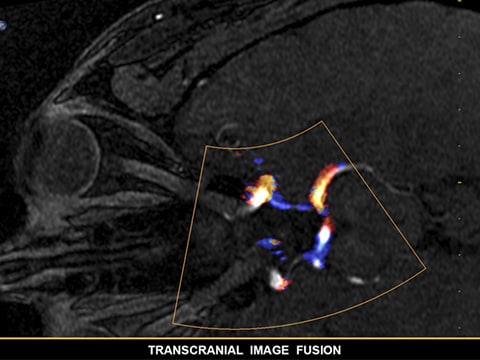

EPIQ CVxi Transcend Plusはインターベンションエコーガイダンスの新しい方向性を示す製品です。要求の高い今日の医療課題を克服するため、多様な患者様およびインターベンション手技に対応する各種の臨床性能を備えています。装置上から直接、ライブフュージョンイメージングであるEchoNavigatorを操作することができ、合理化されたワークフローを実現します。